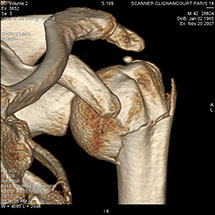

• Les examens et mesures orthopédiques (malformations, fractures et évolution, étude de la structure osseuse).

Le scanner comporte un lit d'examen, sur lequel le patient est allongé, qui va se déplacer lentement pendant l’examen et un anneau qui va tourner autour du patient en émettant des rayons X (il contient le tube à rayons X et les récepteurs). Les rayons X vont traverser la région à étudier et permettre d’obtenir des images en coupe de la zone à étudier. Des traitements de numérisation informatique permettront d'obtenir  des images 2D ou 3D dans différents plans et volumes.